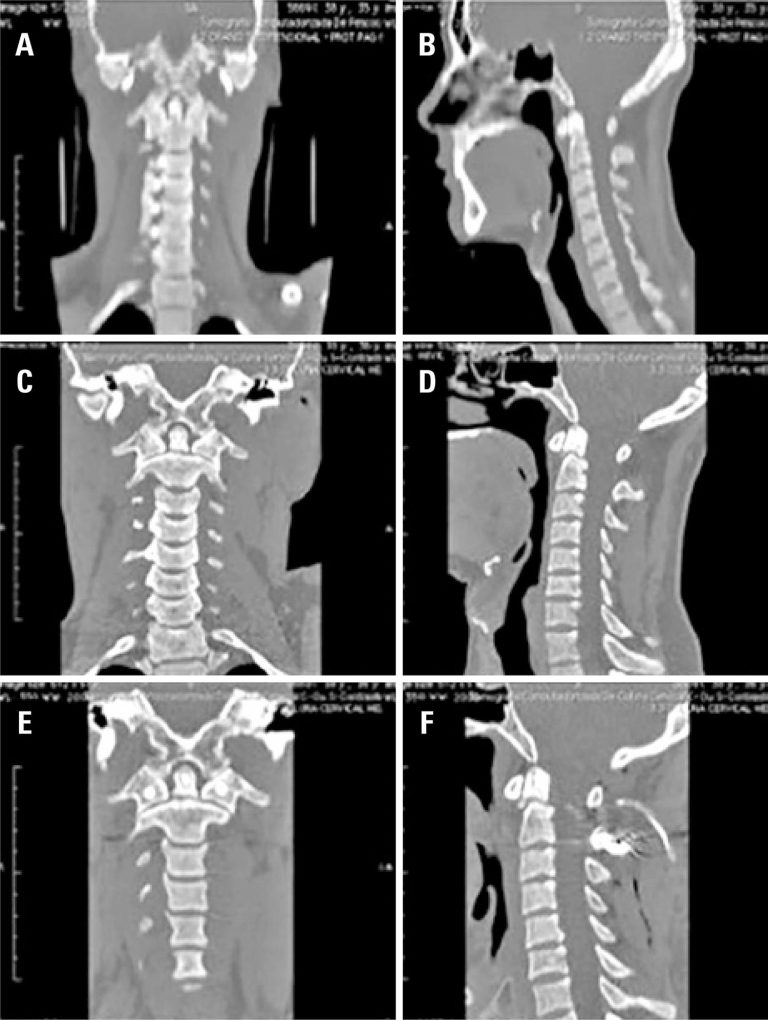

Foram analisados 37 pacientes, 73% eram do sexo masculino e a média de idade foi de 41,7 anos. Inicialmente 32% dos pacientes foram submetidos a tratamento cirúrgico, e 68% foram submetidos a tratamento conservador. Sete pacientes (29%) do grupo conservador foram submetidos posteriormente à cirurgia. No grupo cirúrgico, houve sete casos de fratura de odontóide tipo II, dois casos de fratura de elementos posteriores do áxis, um caso de luxação C1-C2, um caso de deslocamento occipito-cervical e um caso de fraturas de C1 e C2 e luxação facetária. Um paciente apresentava déficit neurológico, melhorando após o tratamento. Houve duas complicações pós-cirúrgicas, uma fístula liquórica e uma infecção de ferida operatória (reabordada). No grupo conservador, predominaram as fraturas do odontóide (oito) e dos elementos posteriores de C2 (cinco). Em dois casos, havia também fraturas em outros segmentos da coluna. Nenhum dos pacientes deste grupo apresentou deterioração neurológica.

As lesões da junção craniocervical são raras, sendo mais frequentes as fraturas do odontóide e dos elementos posteriores do áxis. Nossos resultados recomendam o tratamento cirúrgico precoce para os pacientes com fraturas do odontóide tipo II e lesões ligamentares, e tratamento conservador para os demais pacientes.